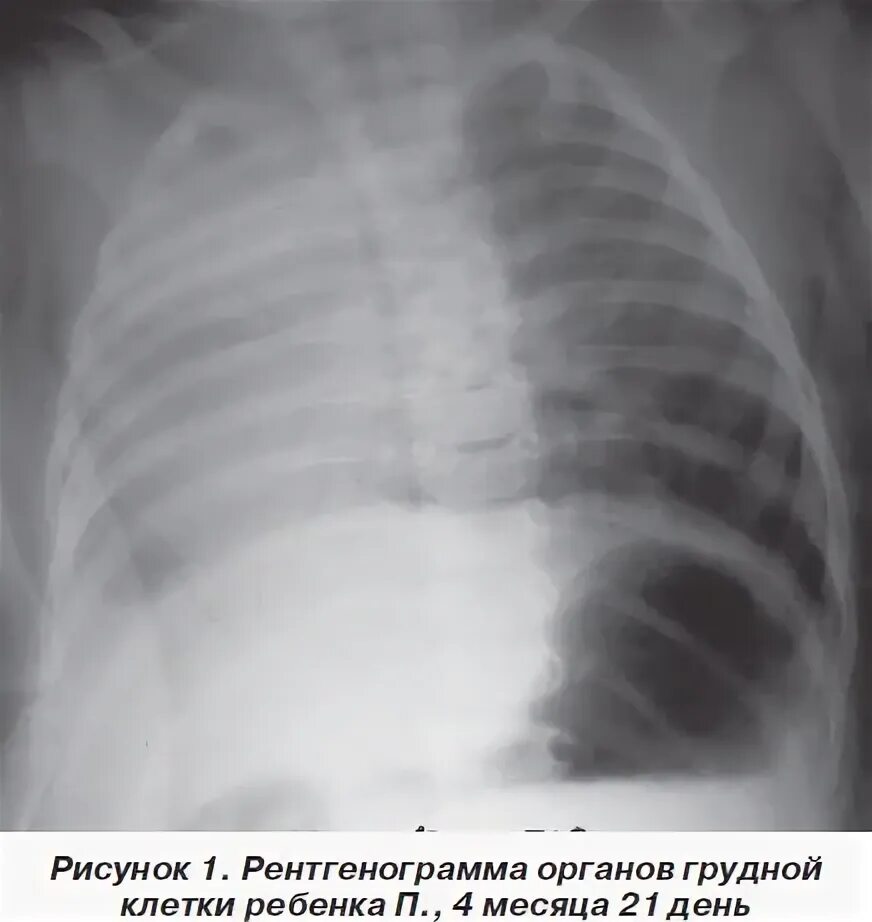

Гипоплазия 12 пары ребер